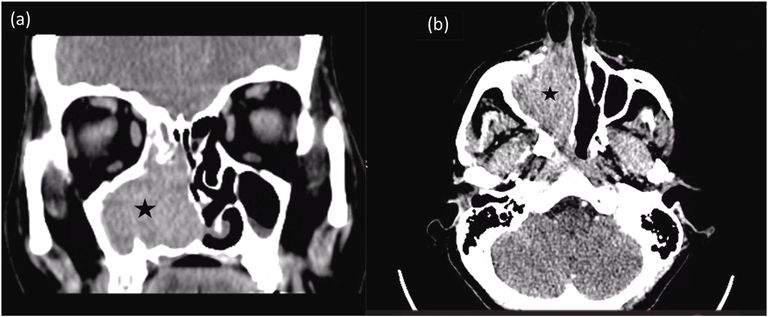

وبحسب التقرير الذي تنشره في مارس/آذار دورية "أوتولرنغولجي كيس ريبورتس "، وحصلت "العين الإخبارية" على نسخة منه، فقد راجعت سيدة تبلغ من العمر 54 عاما عيادة الأنف والأذن والحنجرة بمستشفى المواساة الجامعي بكلية الطب جامعة دمشق بعد معاناة استمرت خمسة أشهر من نزيف أنفي متكرر في جهة واحدة، وانسداد في الأنف، وفقدان لحاسة الشم، وأظهر الفحص بالمنظار وجود كتلة لحمية نازفة تملأ التجويف الأنفي الأيمن وتمتد إلى أرضية الأنف والحاجز الأنفي، بينما بدت بقية فحوصات الرأس والرقبة طبيعية.

ولتأكيد التشخيص، خضعت المريضة لفحوصات نسيجية وتحاليل مناعية، أظهرت جميعها أن الكتلة عبارة عن ورم ميلانيني مخاطي في الجيوب الأنفية، وهو نوع يُعرف بتشابه أعراضه مع أمراض أقل خطورة، مما يزيد من احتمالات تأخر اكتشافه.

ويؤكد التقرير أهمية الفحص بالمنظار، والتصوير المقطعي أو بالرنين المغناطيسي، يليه أخذ خزعة وفحص مناعي لتحديد الورم بدقة.